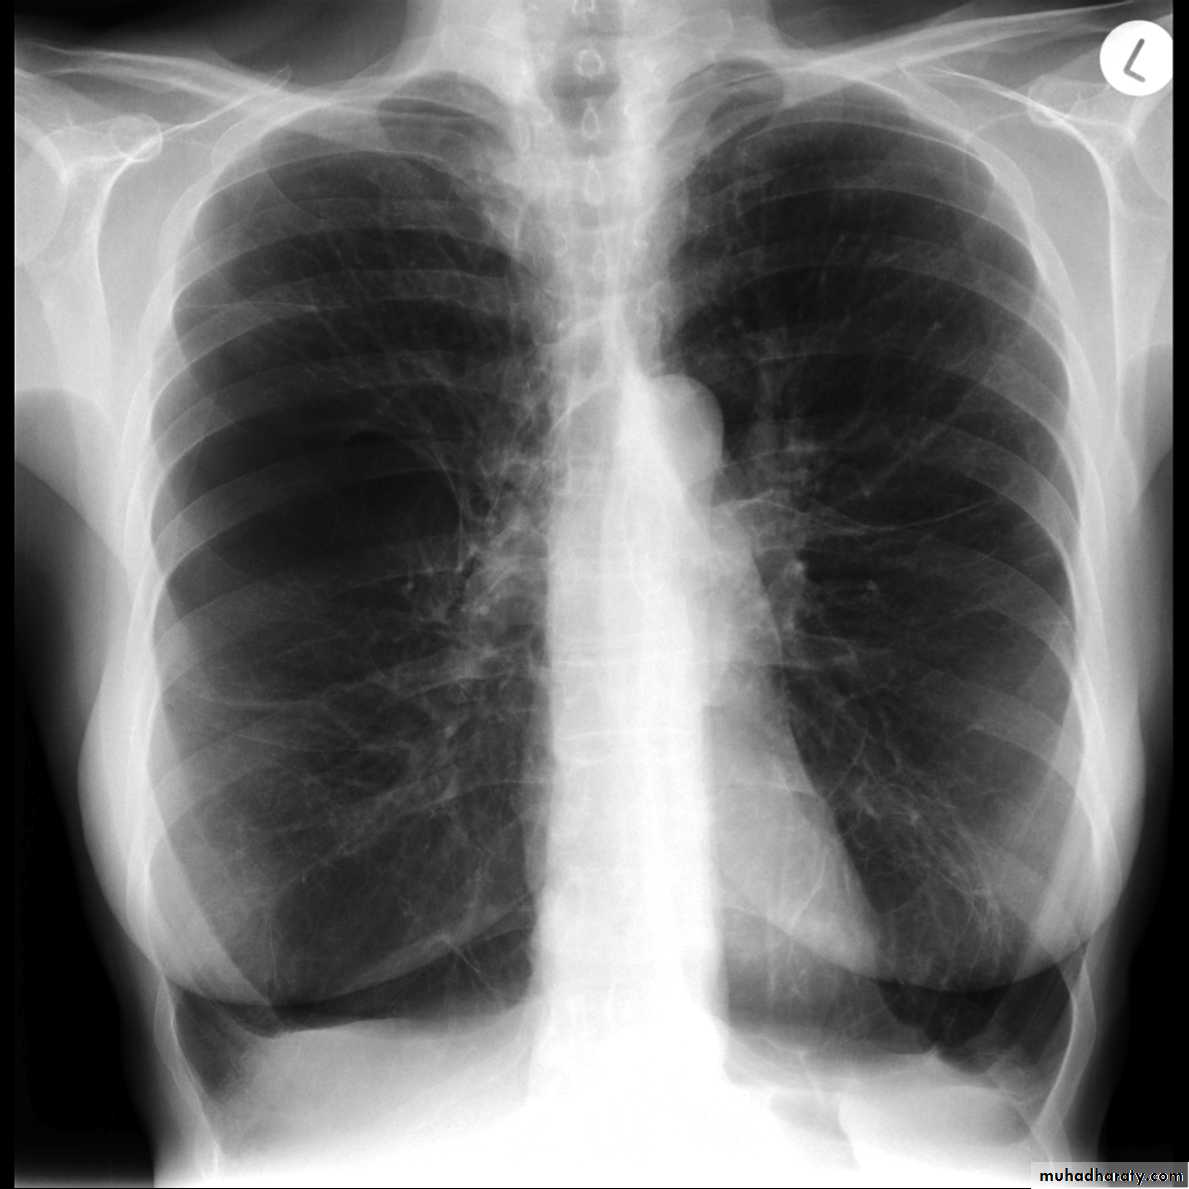

Dextro cardia

Interstitial pulmonary edema

21.Dextrocardia .